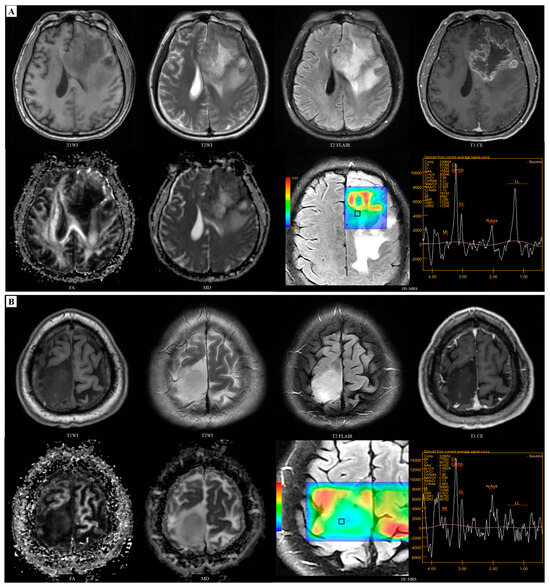

3.3. Models Development for Predicting MGMT

3.4. Performance of Prediction Models